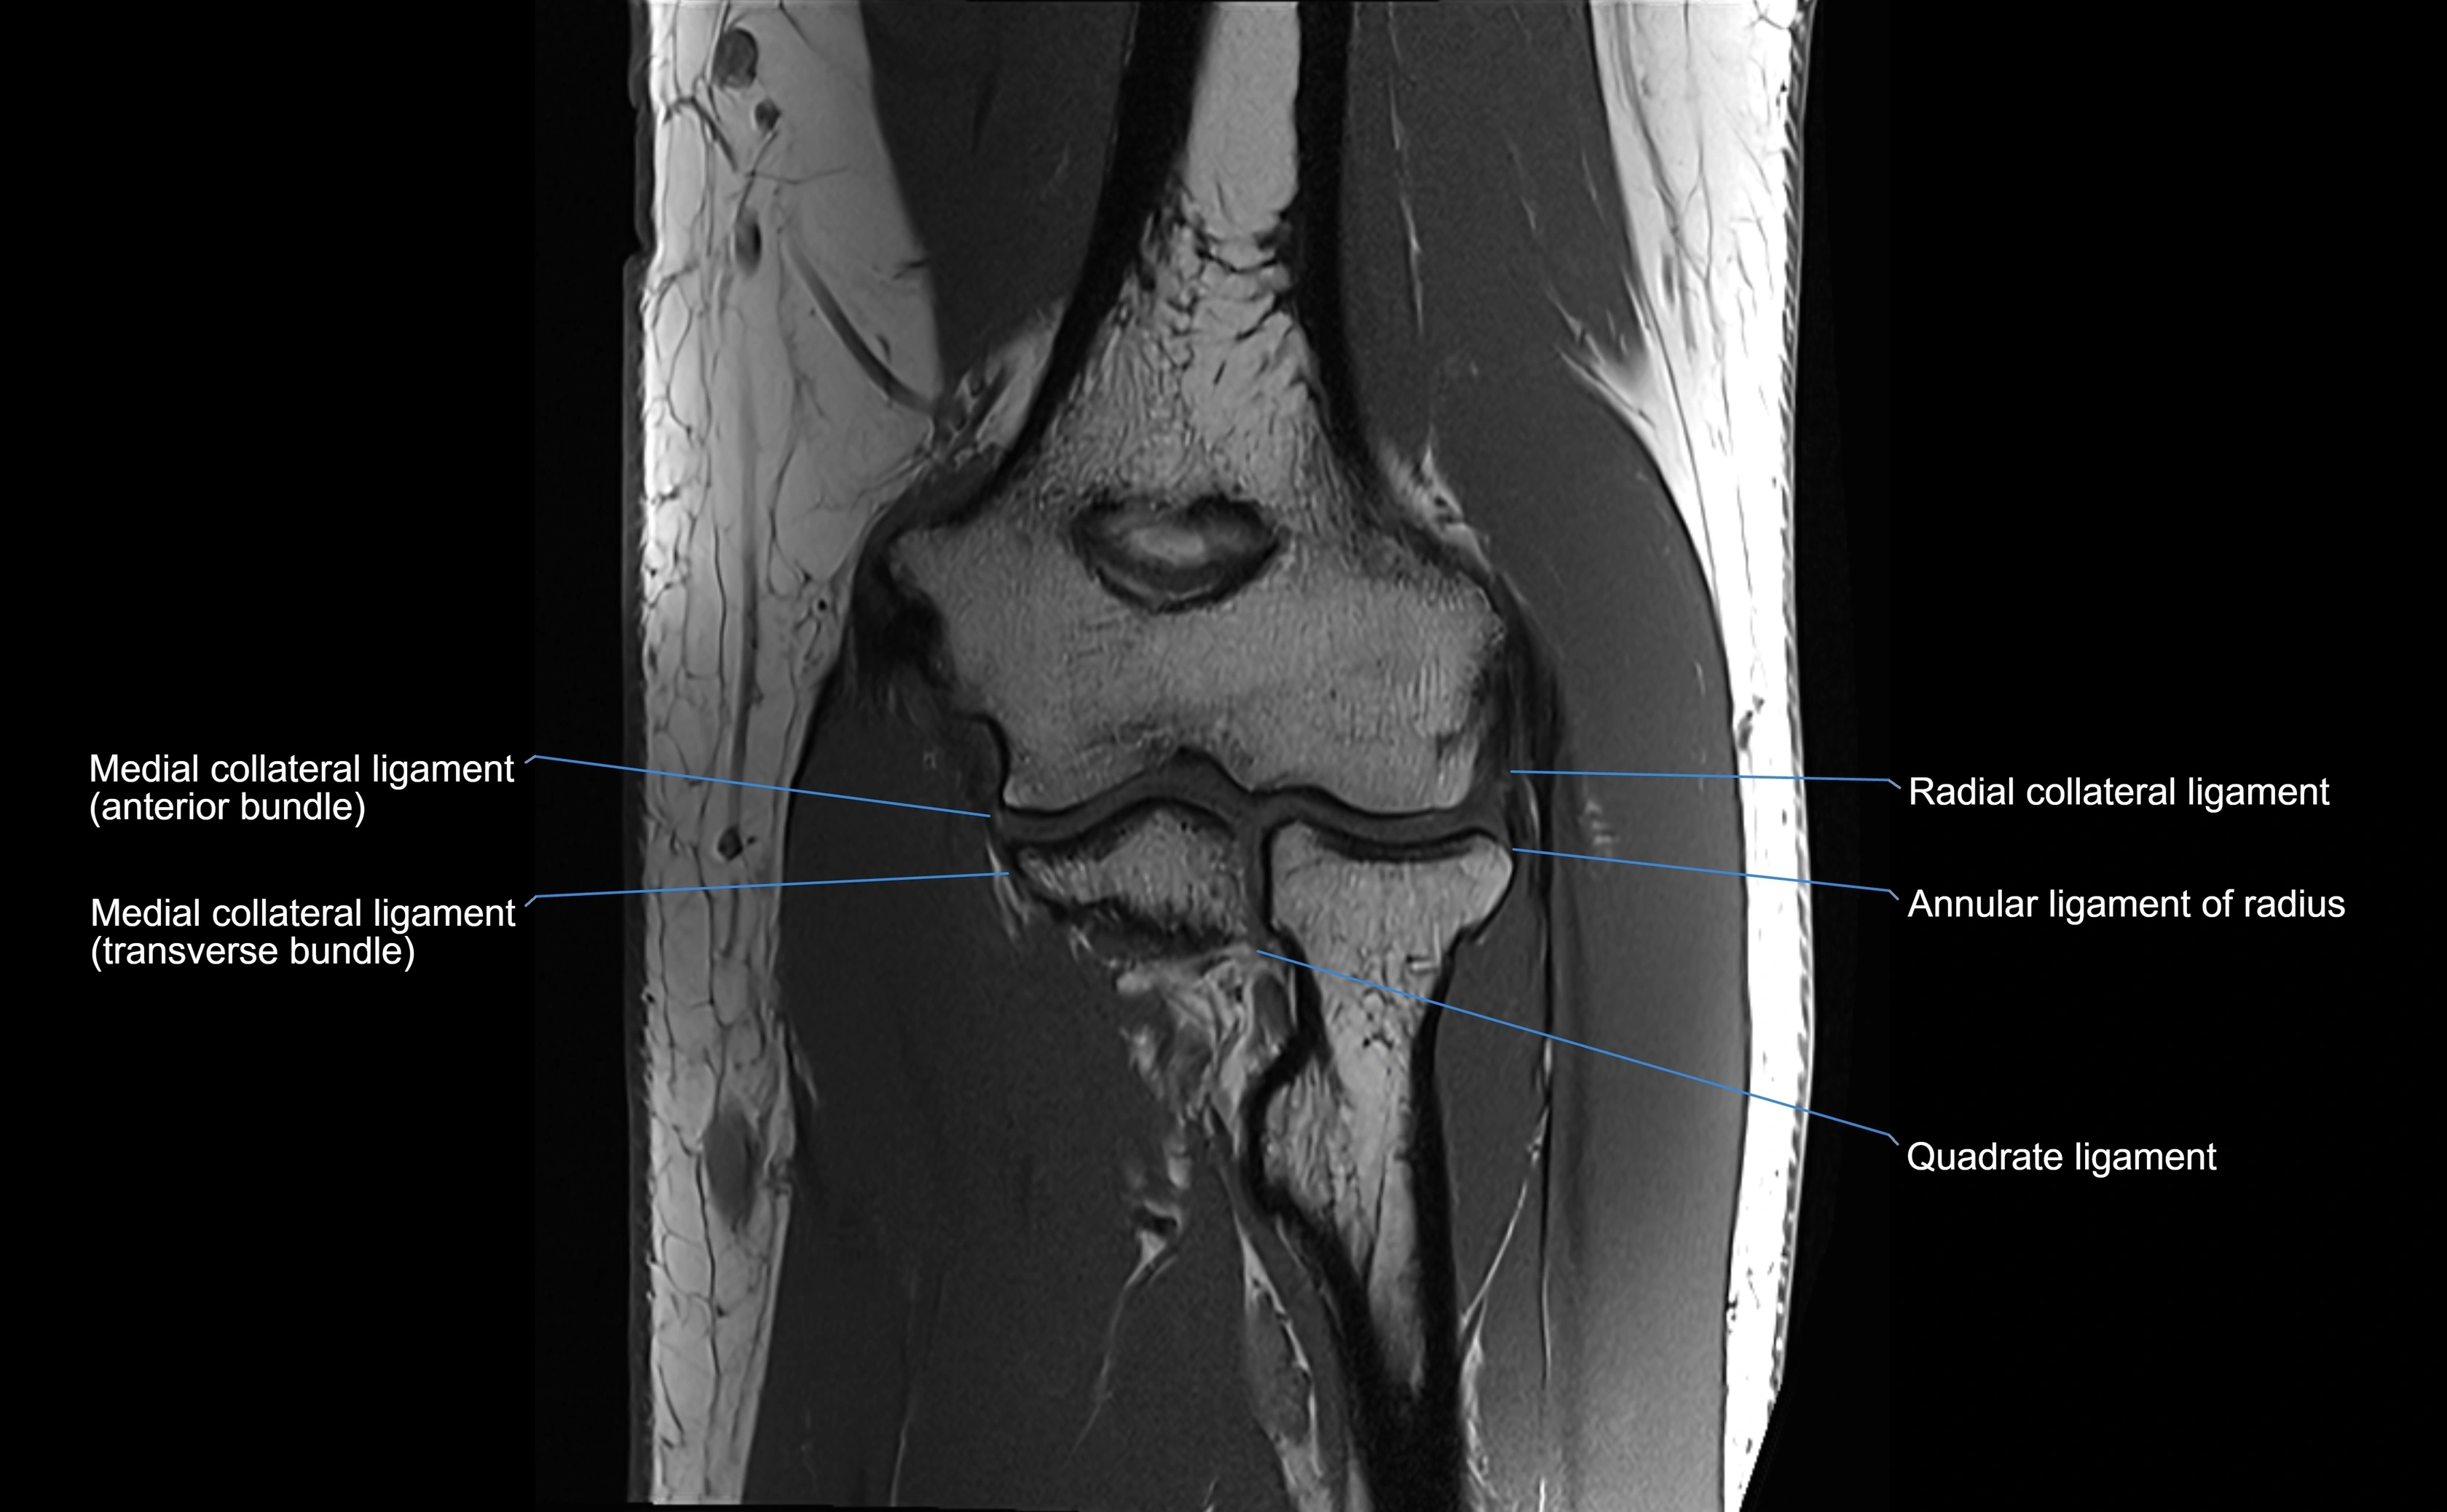

MRI Appearance

T1-weighted images:

• Ligament: low signal intensity (dark), appearing as a continuous band around the radial head.

• Adjacent fat and marrow: bright, creating contrast with the ligament.

• Thickening or disruption indicates injury or fibrosis.

• Joint capsule and synovium seen as thin low-signal lines contiguous with ligament margins.

T2-weighted images:

• Ligament: low signal (dark) with clear delineation from joint fluid.

• Fluid or edema: bright hyperintense, separating or surrounding the ligament in partial tears.

• Complete tear: discontinuity or non-visualization of ligament fibers, often with joint effusion.

MRI images

image